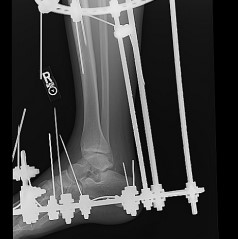

Термінові показання: Відкриті переломи, вивихи, судинні або неврологічні ускладнення вимагають невідкладного втручання для репозиції та стабілізації

Методи фіксації: Сучасні методики включають остеосинтез гвинтами (канюльованими або кортикальними), пластинами або їх комбінацією. Анатомічна репозиція суглобових поверхонь є критичною для профілактики посттравматичного артрозу. Фіксація має забезпечувати достатню стабільність при мінімальному порушенні васкуляризації.